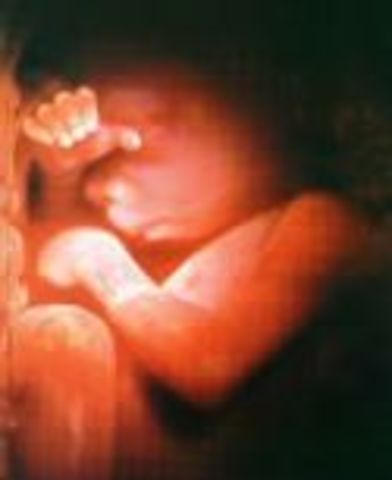

• Week 24: Practices Breathing

Week 24: Practices Breathing

If the baby is born at this stage it has a chance of survival even if it is very early on. While the lungs are developing more, the baby practices breathing by inhaling the liquid it swims in.